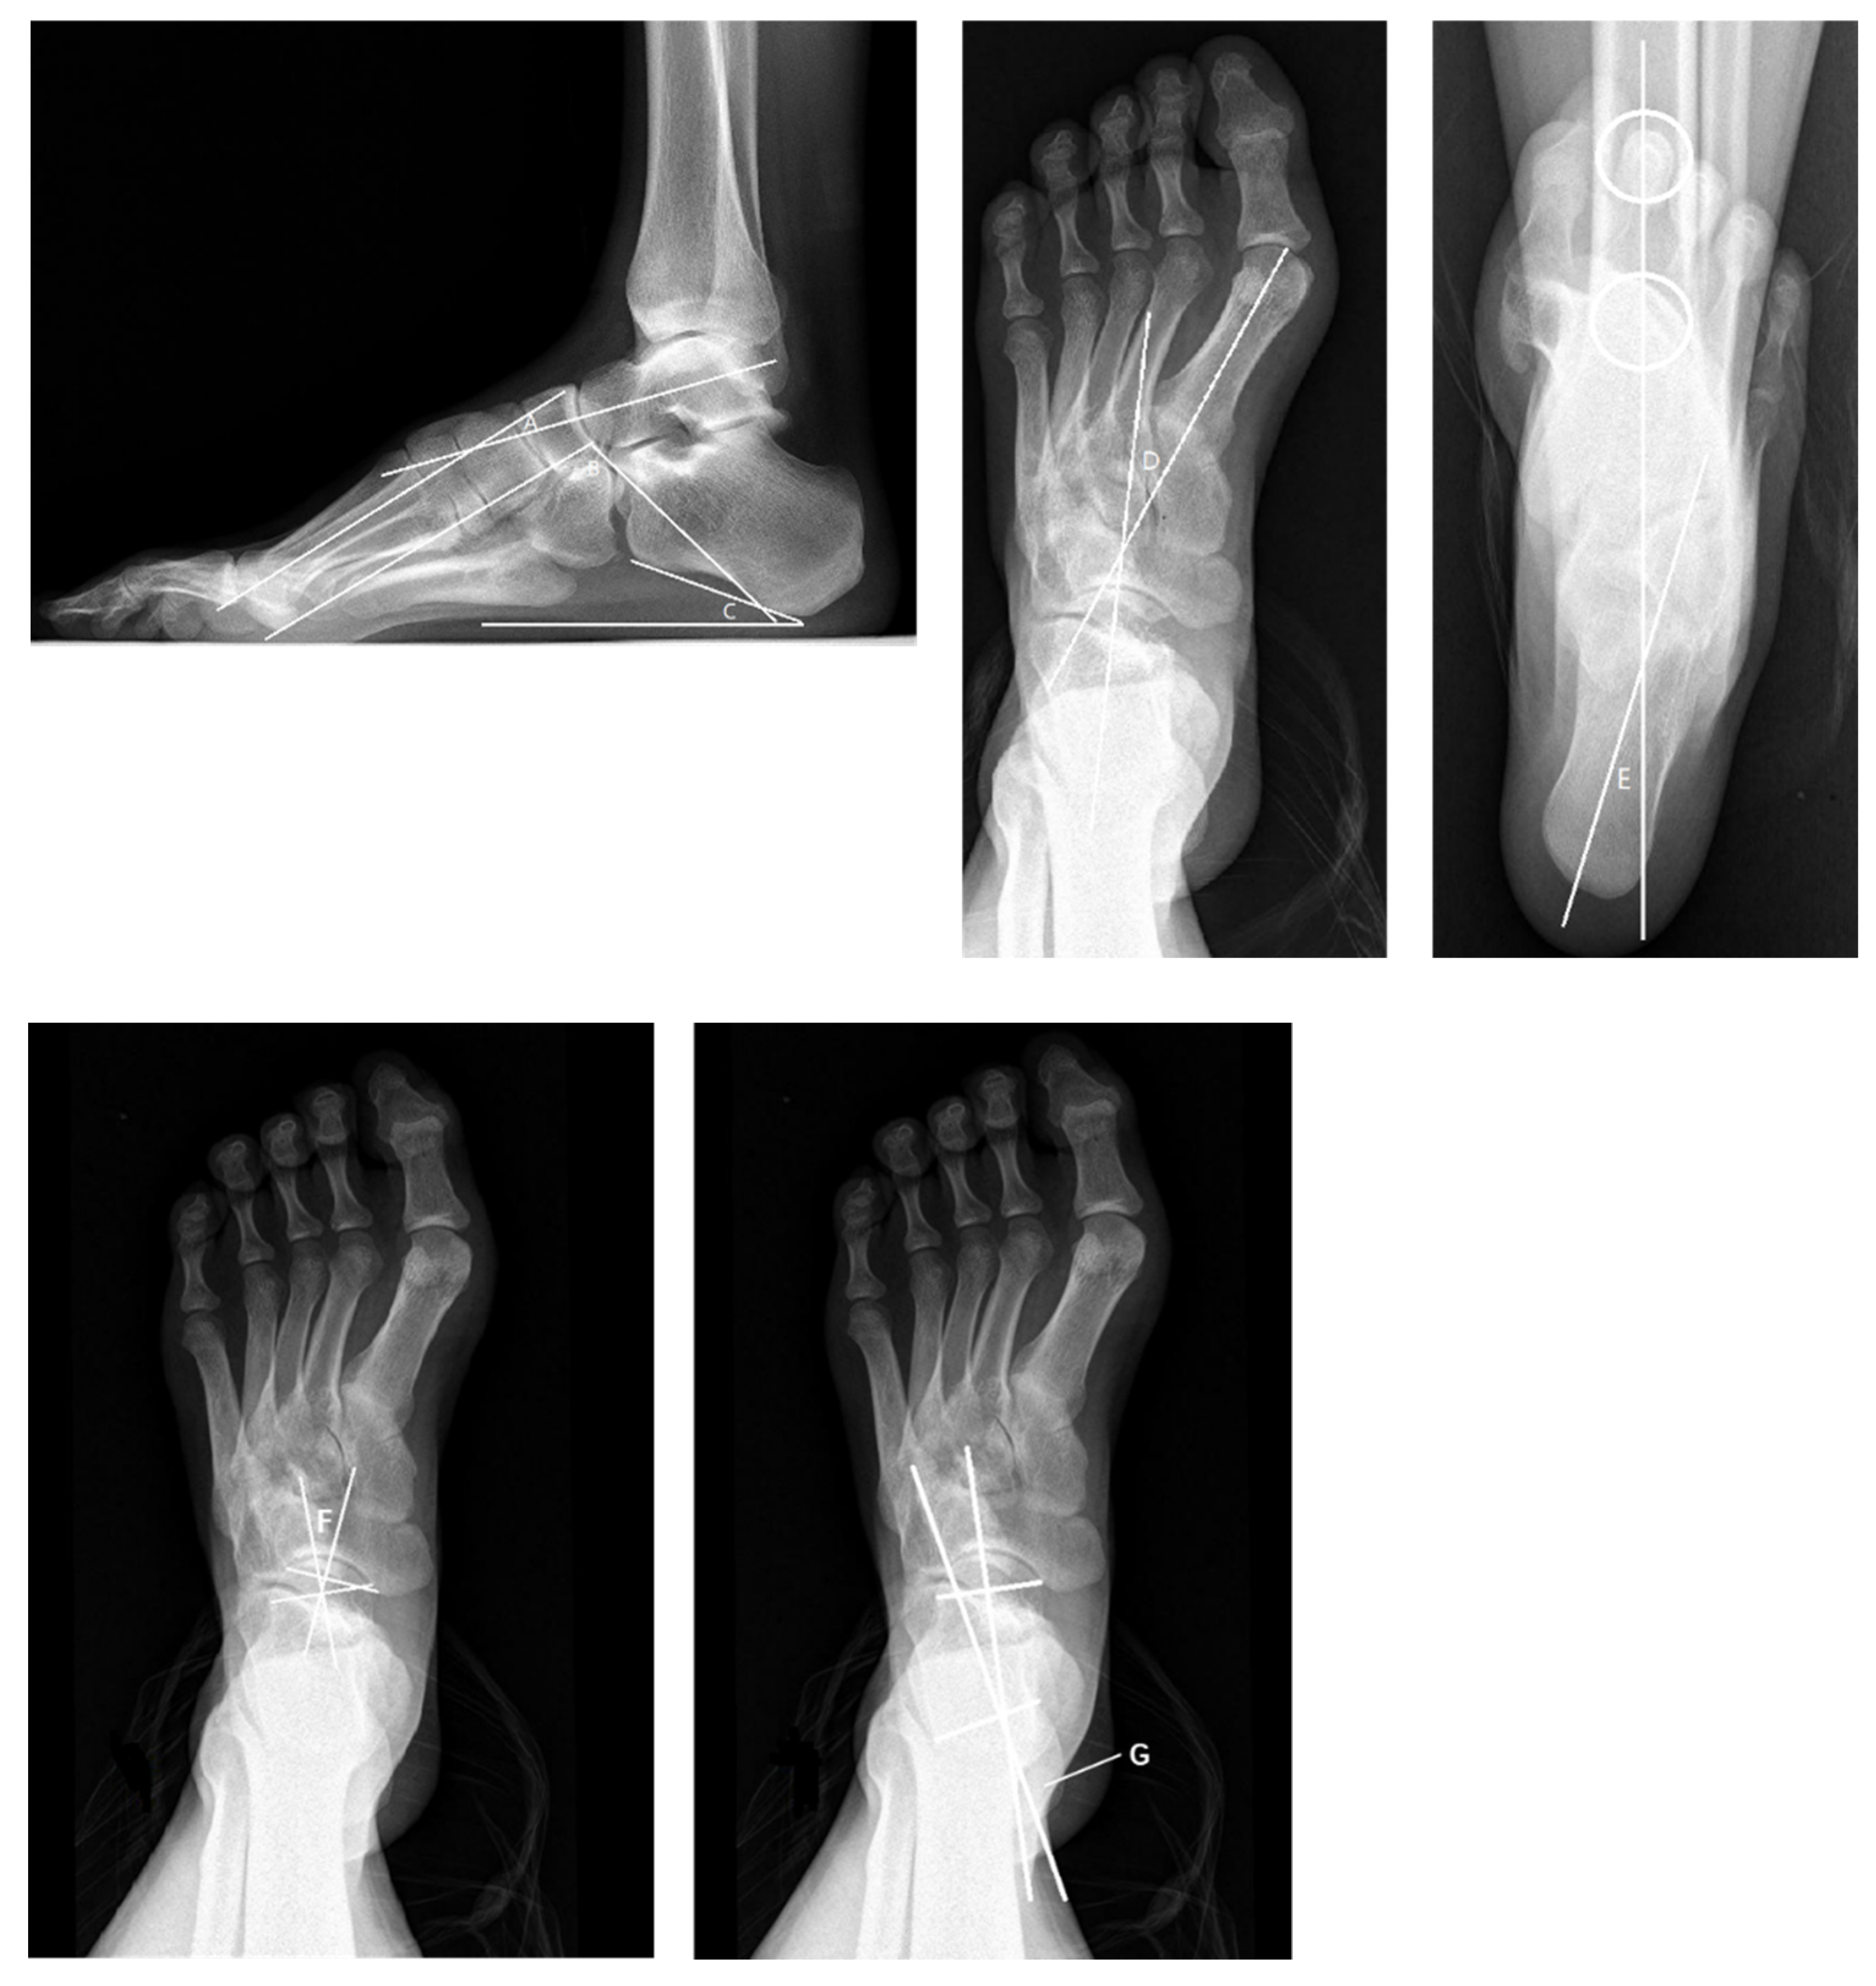

4.2. Radiological Evaluation